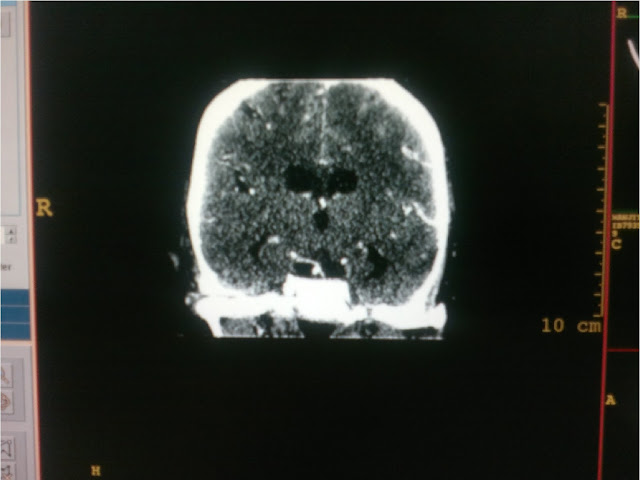

A

56 year old female presented in our OPD with history of headache for past one

month . She has had an episode of severe headache followed by loss of

consciousness . CT head plain revealed Sub arachnoid haemorrage in sylvian

fissure and basal cisterns more on left side. CT angiogram revealed multiple

aneurysms: Pcom on left side which was large approx1.5 x 2 cms and small DACA( Distal anterior Cerebral

artery)2 x 3 mm and small Right MCA aneurysm

measuring 4 x 5 mm in size . Also patient had full Fetal type posterior

circulation on left side . Due to location of

SAH and large size of Pcom aneurysm it was identified as site of

rupture. Large size of aneurysm and Fetal posterior circulation made surgery

risky and there was increased risk of ischaemic deficits in posterior

circulation if Fetal Pcom was accidently

clipped during surgery. However Large

Pcom aneurysm was successfully operated

by us and patient was discharged without any deficit.

ANGIGRAPHY

IMAGES SHOWING MULTIPLE ANEURYSMS WITH

LARGE PCOM ANEURYSM

CT ANGIOGRAM SHOWING ABSENT P1 ON LEFT SIDE AND

P2 FILLING VIA LARGE P-COM